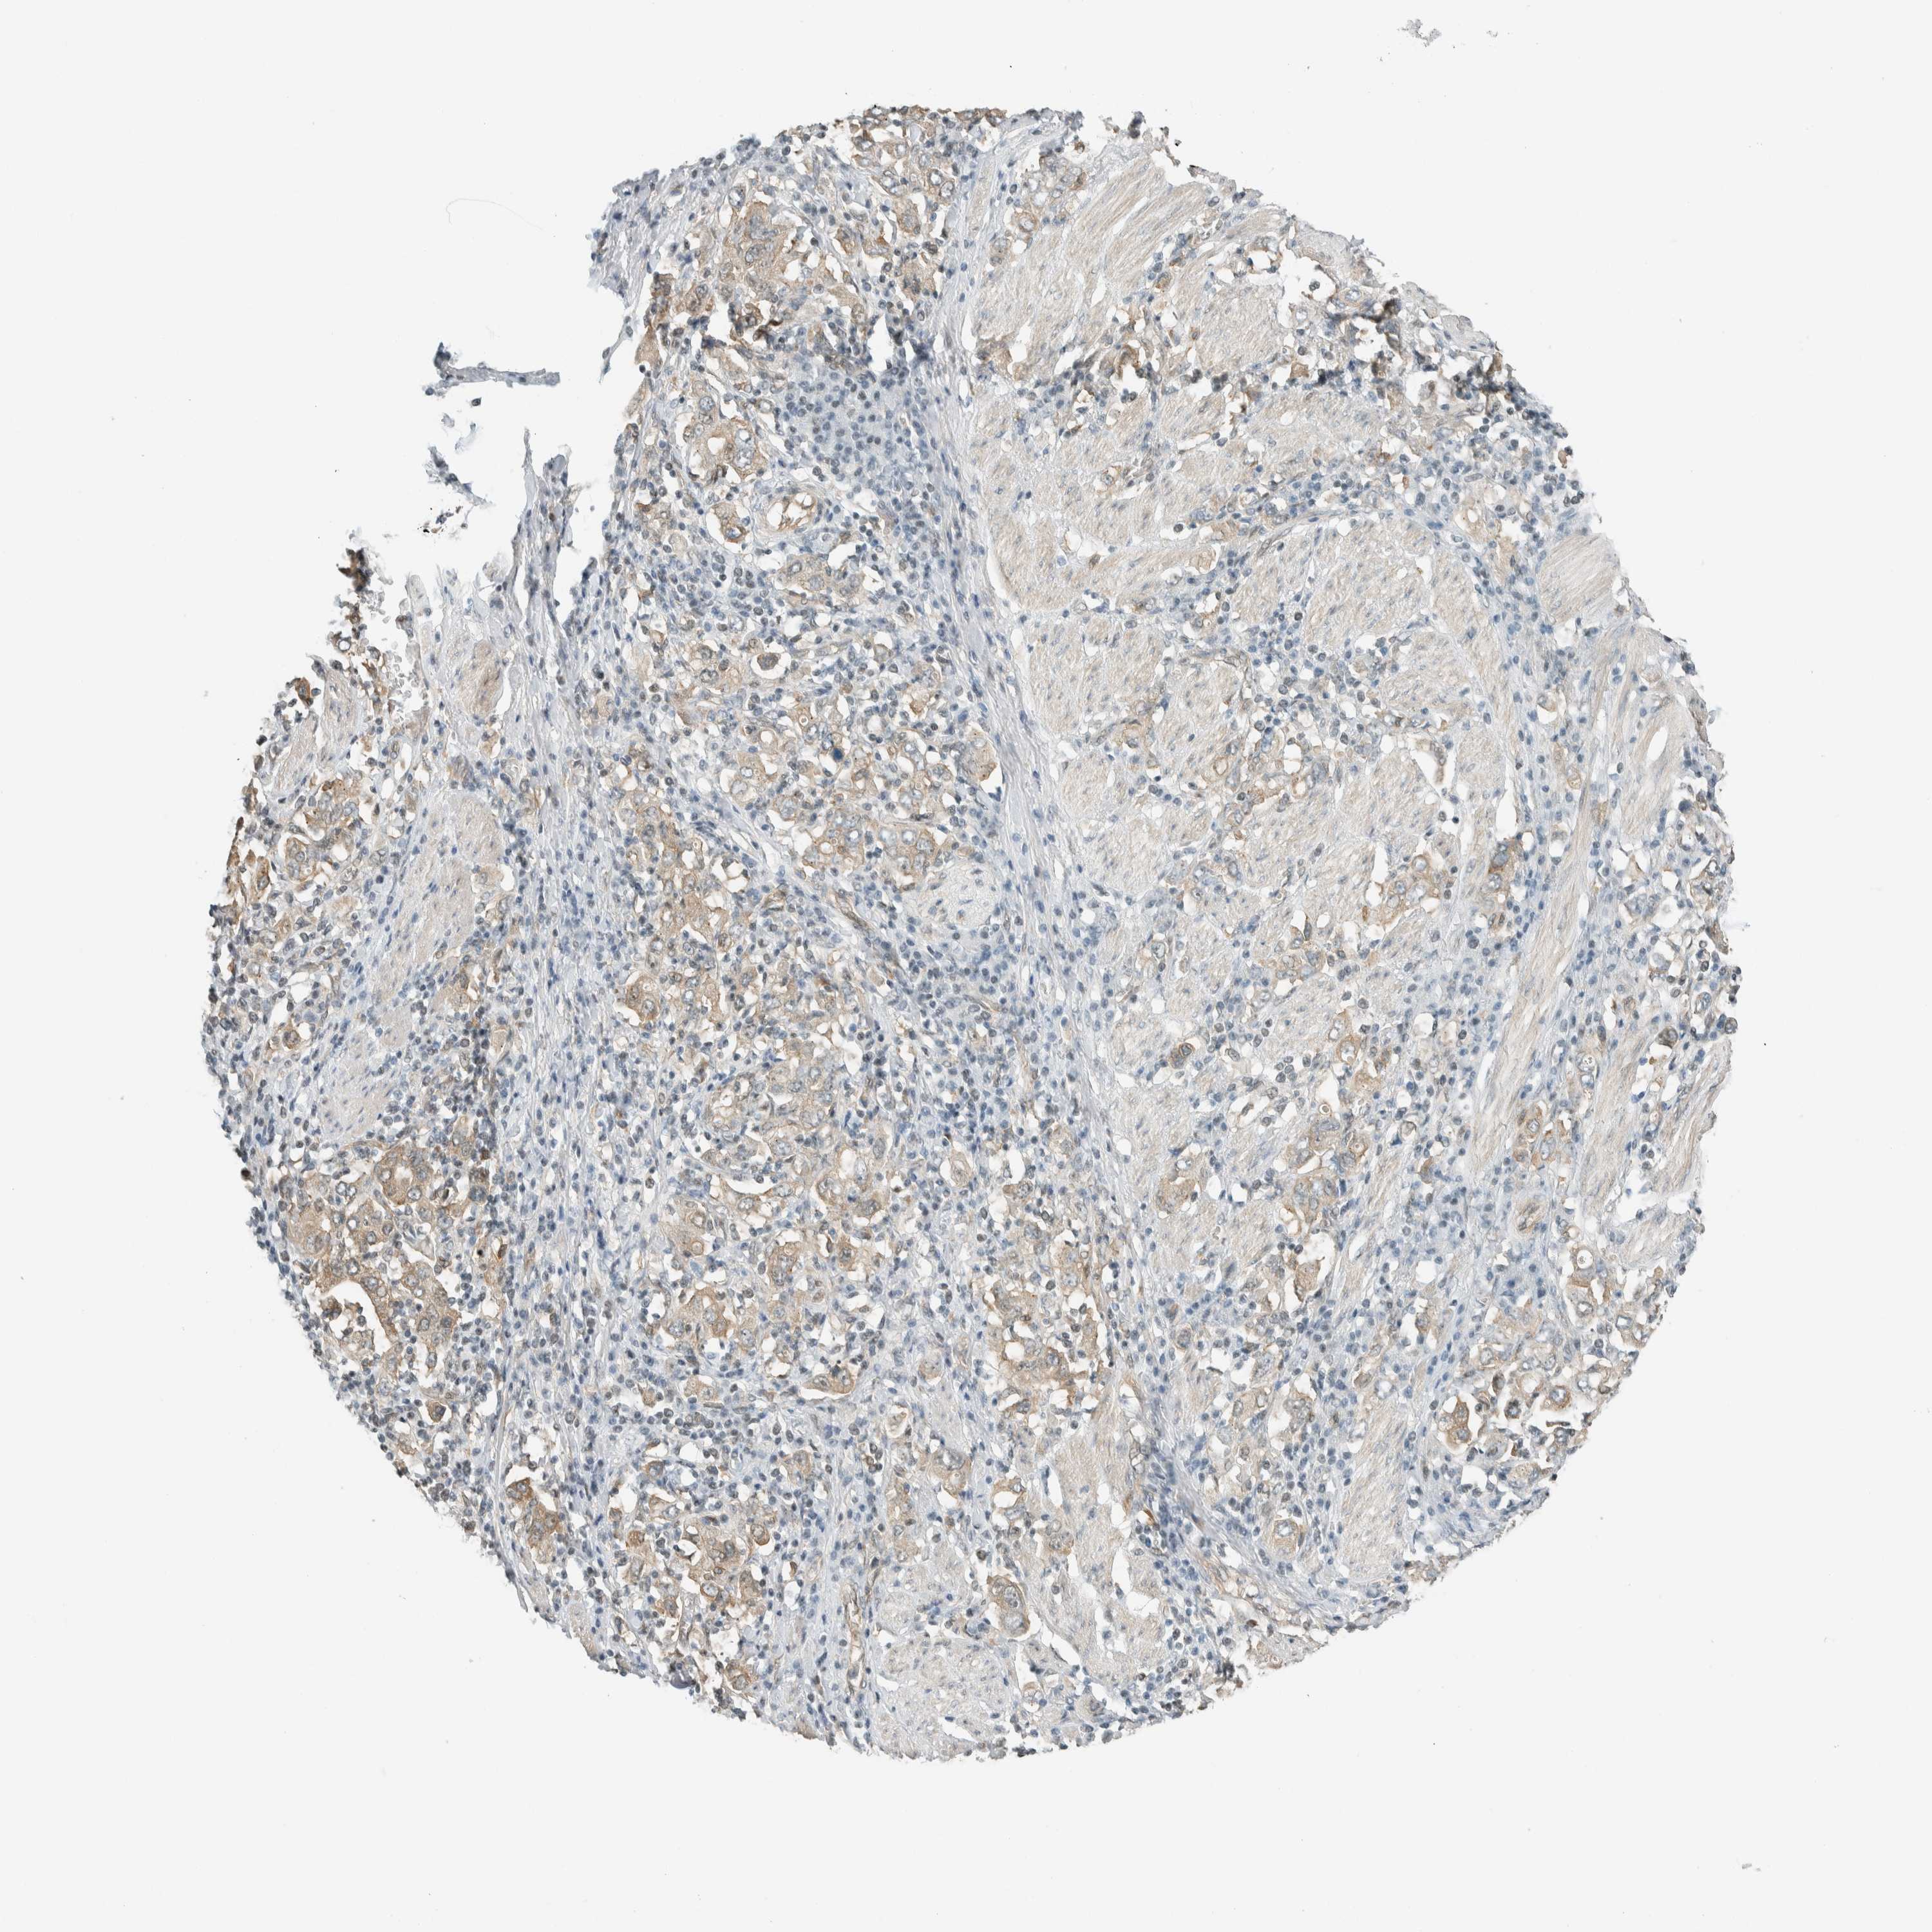

STOMACH CANCER - Protein expressioni

A mouse-over function shows sample information and annotation data. Click on an image to view it in a full screen mode. Samples can be filtered based on level of antibody staining by selecting one or several of the following categories: high, medium, low and not detected. The assay and annotation is described here.

Note that samples used for immunohistochemistry by the Human Protein Atlas do not correspond to samples in the TCGA dataset.

Antibody stainingi

Antibody staining in the annotated cell types in the current human tissue is reported as not detected, low, medium, or high, based on conventional immunohistochemistry profiling in selected tissues. This score is based on the combination of the staining intensity and fraction of stained cells.

Each image is clickable and will lead to virtual microscopy that enables deeper exploration of all samples and also displays staining intensity scores, fraction scores and subcellular localization as well as patient and tissue information for each sample.

Antibody HPA021284

Antibody HPA021417

Antibody HPA023261

Antibody HPA024312

Staining

High

Medium

Low

Not detected

Intensity

Strong

Moderate

Weak

Negative

Quantity

>75%

75%-25%

<25%

None

Location

Nuclear

Cytoplasmic/membranous

Cytoplasmic/membranous,nuclear

Adenocarcinoma, NOS